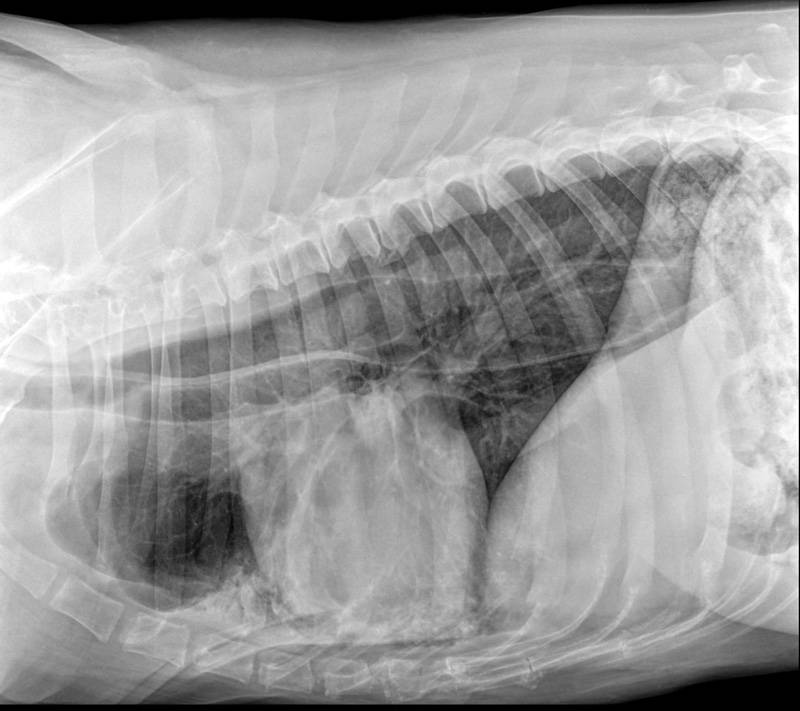

В клинике собаке сделают рентген, который подтвердит или опровергнет отек легких, а также проведут осмотр собаки, прослушают ее и выполнят ряд лабораторных исследований.

Для диагностики отека легких у собак используются такие методы, как аускультация, рентгенография грудной клетки или ультразвуковое исследование, также требуется анализ крови. Электрокардиограмма, анализ мочи и измерение кровяного давления — другие важные тесты, позволяющие выяснить, есть ли у вашей собаки отек легких.

Если состояние вашего питомца стабильное, можно выполнить рентгенографию грудной клетки, положив собаку на спину. На этой рентгенограмме могут быть признаки отека легких, такие как повышенная интерстициальная или альвеолярная непрозрачность. У собак, страдающих кардиогенным отеком легких, также могут наблюдаться кардиомегалия и расширенные легочные вены.

Рентгеновские снимки являются основным инструментом для диагностики отека легких, поскольку они выявляют жидкость внутри легких собаки. Рентген также может выявить увеличенное сердце или другие аномалии сердечной мышцы.